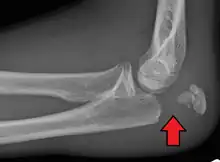

To assess an olecranon fracture, a careful skin exam is performed to ensure there is no open fracture. Then a complete neurological exam of the upper limb should be documented.[5][2] Frontal and lateral X-ray views of the elbow are typically done to investigate the possibility of an olecranon fracture.[1] A true lateral x-ray is essential to determine the fracture pattern, degree of displacement, comminution, and the degree of articular involvement.

Tension band fixation

Tension band fixation is the most common form of internal fixation used for non-comminuted olecranon fractures.[5] It is typically reserved for noncomminuted fractures that are proximal to the coronoid.[2] This procedure is performed using Kirschner wire (K-wires) which converts tensile forces into compressive force.[2]